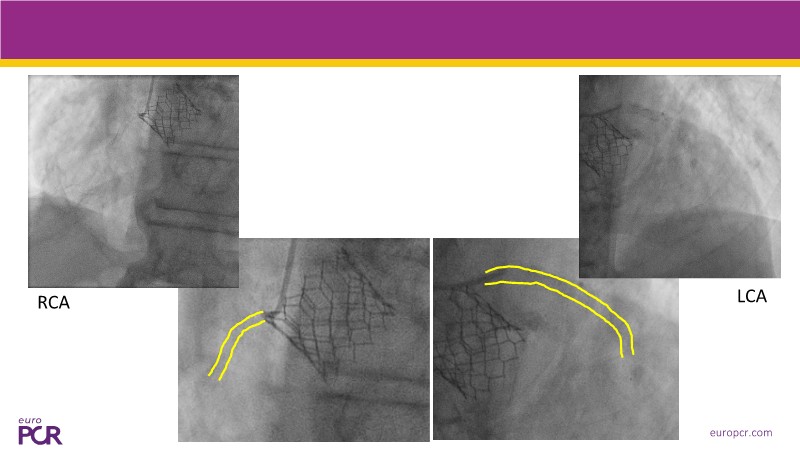

This session explores some of the most clinically complex scenarios encountered in TAVI practice. Three real-world cases address key challenges such as intervention sequencing and transcatheter valve selection in patients with combined coronary artery disease and severe aortic stenosis. The session also examines coronary obstruction risk assessment and protection strategies during redo TAVI, and discusses specific implantation techniques for anatomically complex cases, including large aortic valve anatomy.

- To appreciate the impact of device choice and implantation technique on coronary access and REDO TAVI